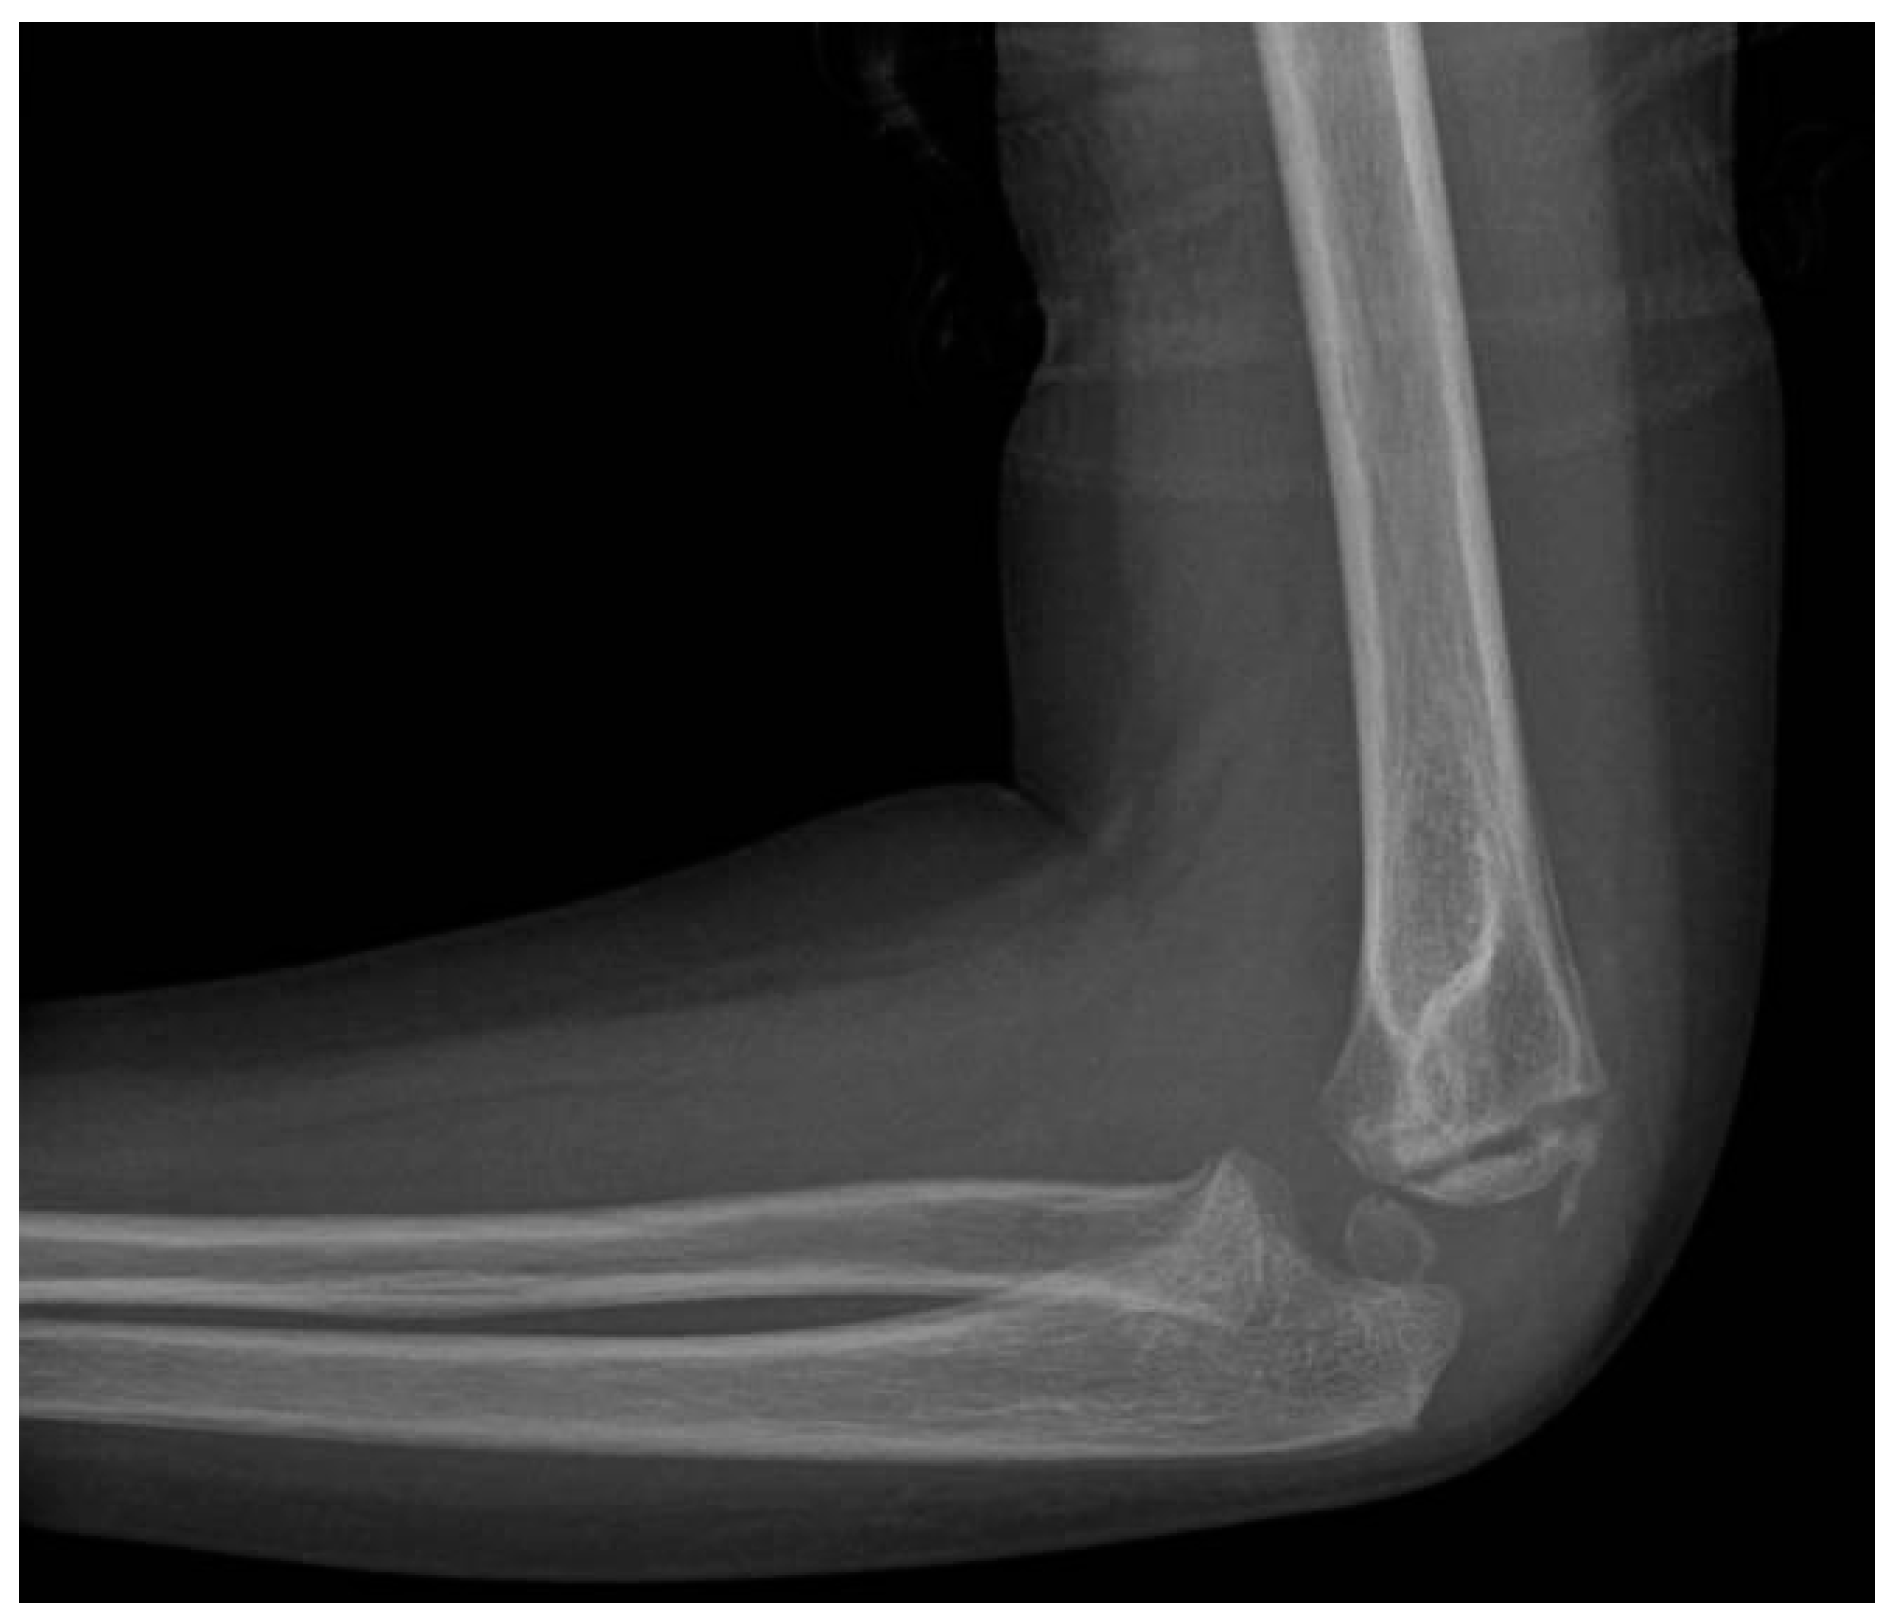

Lateral Humeral Condyle Fracture in Childhood: Results of a New Surgical Technique

1. Introduction